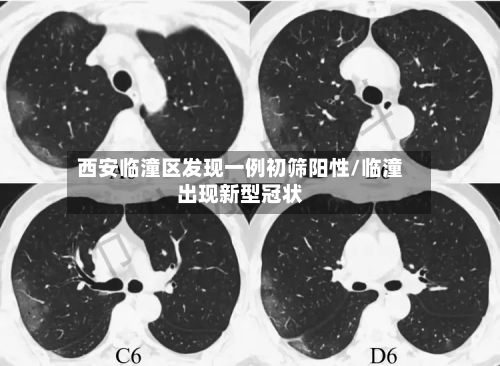

西安临潼区发现一例核酸初筛阳性人员,近来接触人员情况如何?

近来接触人员都已经按照规定报备,并且配合疫情防控的要求 ,接受隔离了。西安临潼区区发现一例核酸初筛阳性人员,近来已这名阳性人员有过间接性接触的人员基本上都已经按照当地的防疫规定向有关部门报备,并且配合相应的防疫措施 ,接受了隔离管控。

月18日,西安市临潼区在集中隔离人员中发现一例无症状感染者 。该病例曾于4月16日12:43至13:37在马额街道有活动轨迹,先后到马额街道旺盛达门业、鸿运建材商店购买建材等。

临潼区紧急寻人 4月18日,西安市临潼区在集中隔离人员中发现一例无症状感染者。该病例曾于4月16日12:43至13:37在马额街道有活动轨迹 ,先后到马额街道旺盛达门业、鸿运建材商店购买建材等。

〖壹〗 、临潼区紧急寻人 4月18日,西安市临潼区在集中隔离人员中发现一例无症状感染者。该病例曾于4月16日12:43至13:37在马额街道有活动轨迹,先后到马额街道旺盛达门业、鸿运建材商店购买建材等 。请4月16日以来去过马额街道的人员 ,立即就近向所在村委会(社区)或疫情防控部门进行报备,并落实从4月16日到21日5天3次核酸检测要求。